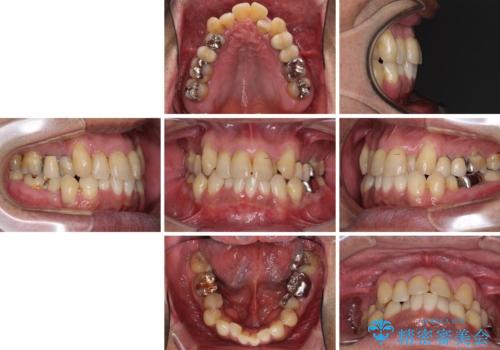

- 前歯がのデコボコや、奥歯に咬んだときに痛みがあるとのことで来院された患者様です。

全体的に問題が多く、全てをしっかりと治療したいとのことでした。

全体的に中等度の歯周病と診断されたため、歯周外科処置やインプラントによる咬合回復から進めて行き、矯正治療による歯列改善を行った後にオールセラミッククラウンにて補綴することとしました。